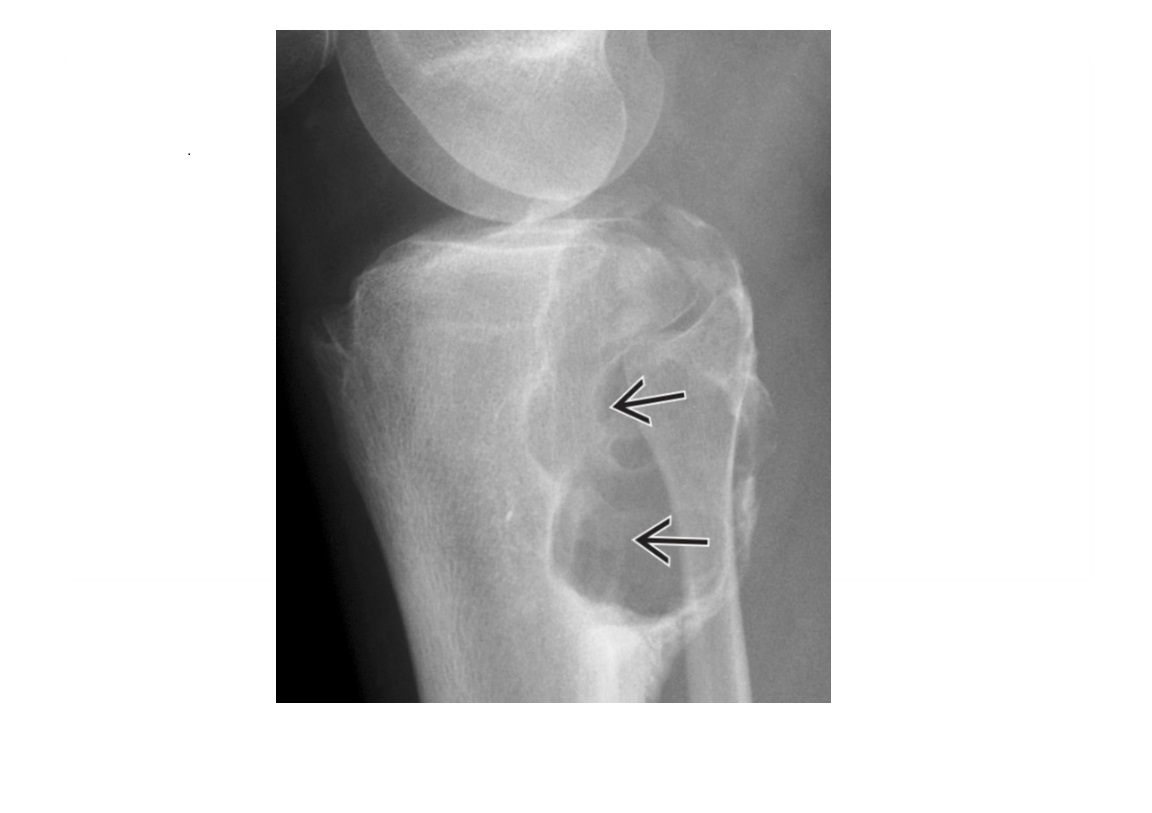

Arcuate sign

Avulsion of the proximal fibula

Associated with PCL tear